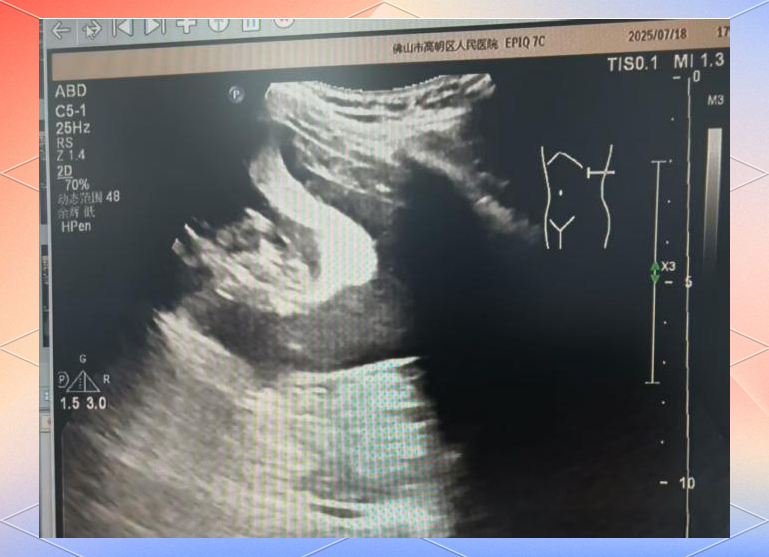

变化的脾囊肿

图片尺寸2080x4624

左侧脾与左肾上极之间可见无回声区,考虑左肾上腺囊肿,彩超与ct对比

图片尺寸3000x1906